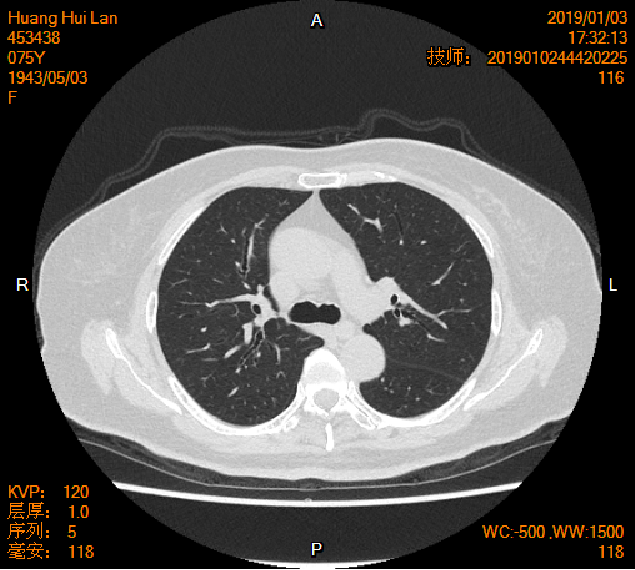

2019-01-04胸腹盆CT